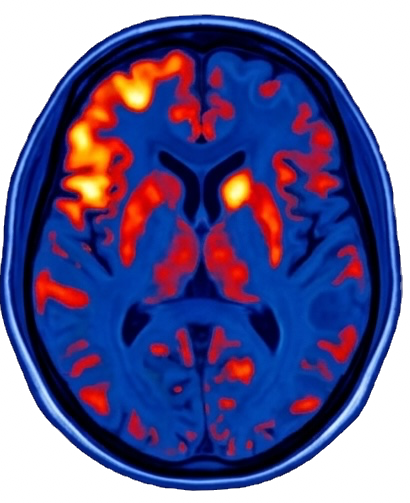

Brain Before TMS vs After TMS treatment